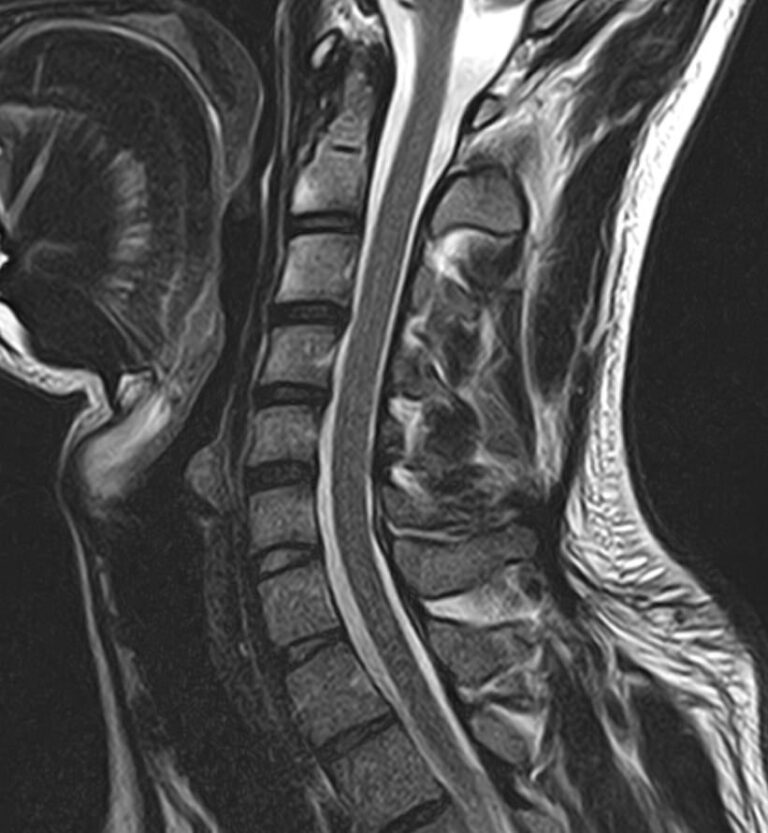

В клинике «Доступная медицина» можно пройти комплексное обследование, включающее в себя несколько протоколов сканирования близко расположенных друг от друга анатомических областей – шейного отдела позвоночника и головного мозга. Метод комплексного обследования оценивает состояние всех структур головного мозга и шейного отдела позвоночника. При этом дополнительные протоколы обследования позволяют визуализировать крупные сосуды шеи и сосудистую сеть головного мозга.

Шейный отдел позвоночника — это самый подвижный сегмент позвоночного столба, который испытывает повышенные нагрузки, подвержен травмам и развитию различных заболеваний. В эту анатомическую область входит 7 верхних позвонков, спинной мозг с отходящими от него нервными корешками.

Часто различные нарушения в шейном отделе позвоночника приводят к ухудшению кровоснабжения головного мозга. Опухоли и дегенеративно-дистрофические заболевания шейного отдела позвоночника могут нарушать работу головного мозга. Атеросклеротические бляшки в сосудах шеи могут стать причиной преходящих нарушений мозгового кровообращения (транзиторных ишемических атак) и привести к развитию инсульта. Поэтому важно в комплексе детально визуализировать эти анатомические структуры вместе с оценкой состояния кровеносной системы головы и шеи.

Сканирование проводится на современном высокопольном магнитно-резонансном томографе закрытого типа TOSHIBA VANTAGE TITAN 1,5 Тесла. Магнитно-резонансный томограф производит послойное сканирование исследуемой зоны в разных плоскостях, затем при помощи компьютерных программ преобразует полученные данные в трехмерные изображения. При этом кровеносная система реконструируется как вместе с окружающими тканями, так и отдельно без них.

• остеохондроз, спондилоартроз, спондилез, межпозвонковые грыжи, унковертебральный артроз, сколиоз, усиленный или выпрямленный лордоз как нарушение статической функции позвоночника, травмы, аномалии позвоночника.